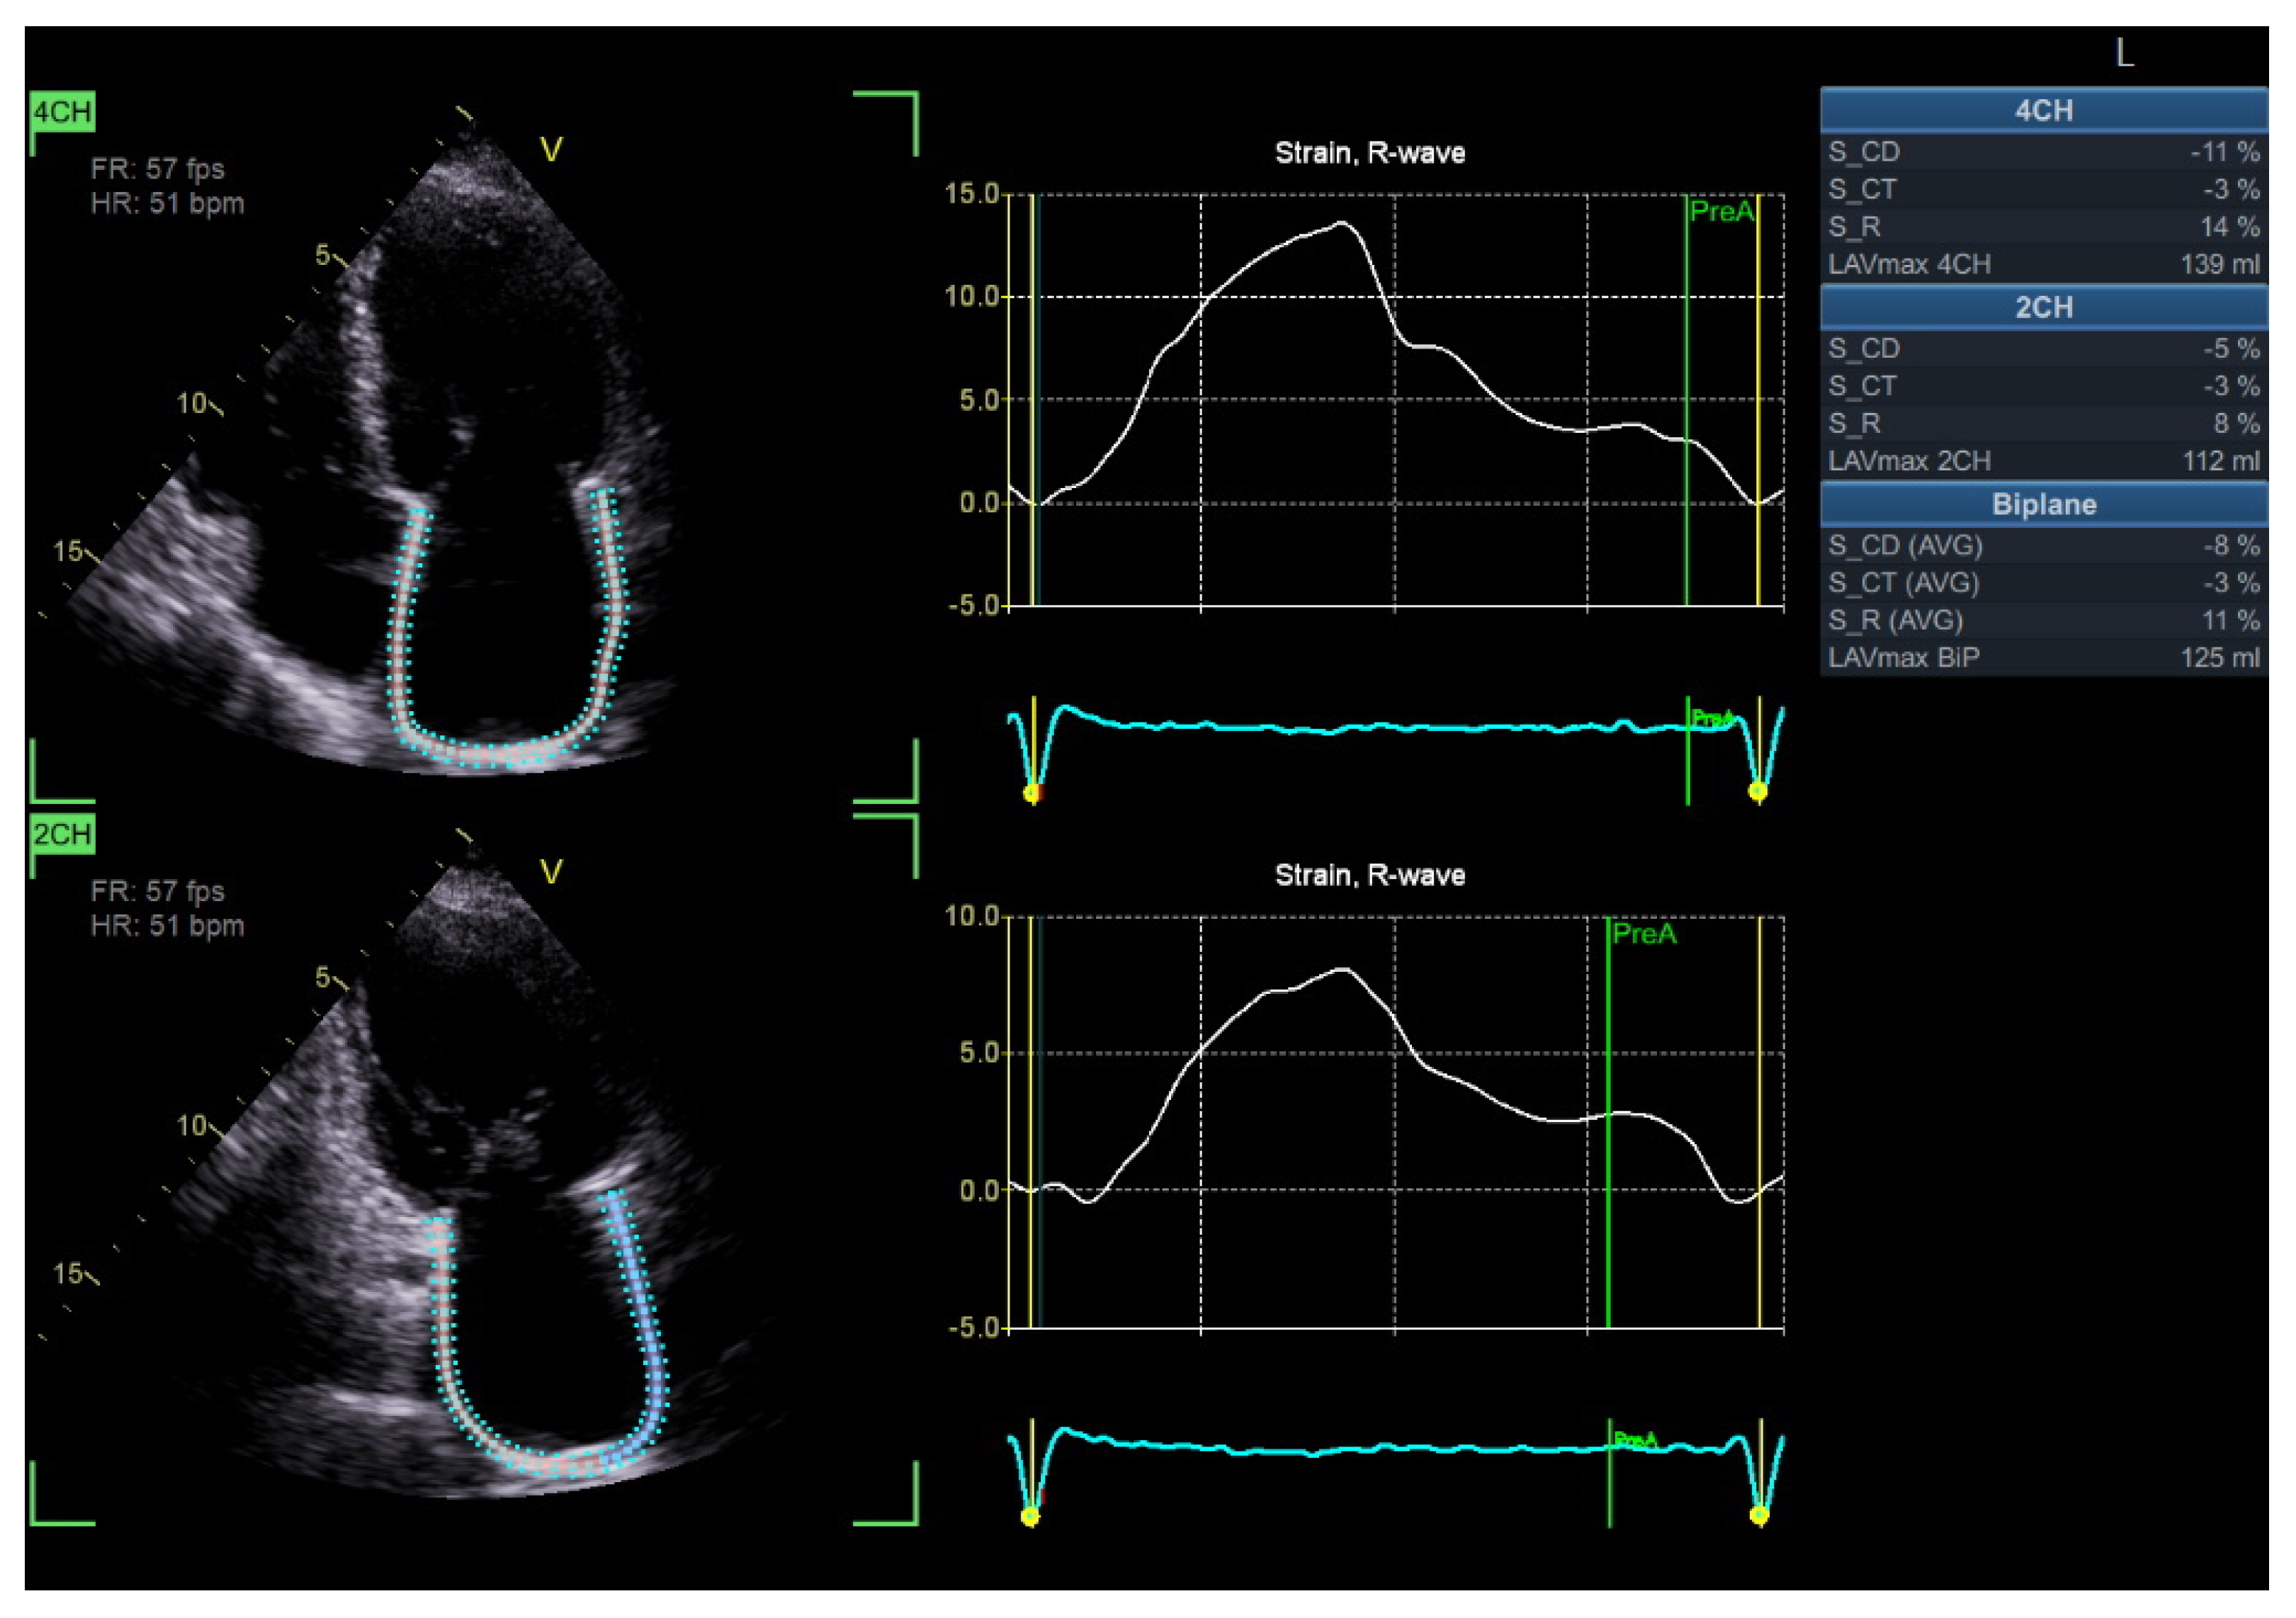

4.3. Speckle Tracking Echocardiography of the Left Atrium

LA function plays a crucial role in maintaining cardiac hemodynamics, particularly in DBCM where diastolic dysfunction is a hallmark feature [80]. LA remodeling and dysfunction have been increasingly recognized as early markers of diabetic heart disease, where alterations in LA strain parameters show superior sensitivity than traditional volumetric assessment [81]. LA STE enables the assessment of three distinct phases of atrial function: reservoir, conduit, and contractile function. Among these, peak atrial longitudinal strain (PALS) and peak atrial contraction strain (PACS) have been identified as sensitive markers of subclinical diastolic dysfunction in diabetic patients [82]. Several studies have reported significantly reduced absolute PALS and PACS values in diabetic individuals compared to controls, with reductions correlating strongly with disease severity and glycemic burden [83].

LA stiffness, as assessed by LA strain imaging, has also been shown to be a strong predictor of elevated LVFP and progression to HFpEF in DM [84]. Additionally, LA strain abnormalities precede LA enlargement, suggesting that strain-based metrics may serve as an early warning system for identifying patients at risk of adverse cardiovascular outcomes [85].

Importantly, emerging data indicate that LA strain analysis may have independent prognostic value beyond conventional echocardiographic indices. A study by Swiatkiewicz et al. demonstrated that impaired LA strain was significantly associated with an increased risk of atrial fibrillation and adverse cardiovascular events in diabetic populations [86]. These findings suggest that LA strain assessment could be integrated into routine echocardiographic screening protocols for diabetic patients, particularly those with suspected diastolic dysfunction (Figure 5).

LA STE analysis is limited by rhythm and heart rate dependency and the lack of standardized reference values. Image quality is again a pre-requisite. The thin atrial wall increases susceptibility to noise, affecting its accuracy. In addition, abnormal septal motion, such as in high atrial loading conditions or interatrial septal aneurysm, may further impair the accuracy and reproducibility of measurements.